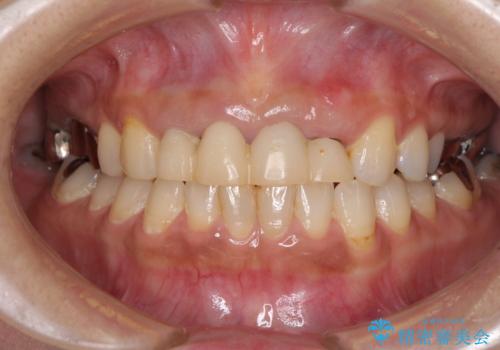

汚れた仮歯が気になる 前歯のオールセラミッククラウン

仮歯を変えたことで歯肉の腫れは引き、根管治療も功を奏して膿の出口はきれいに消退しました。